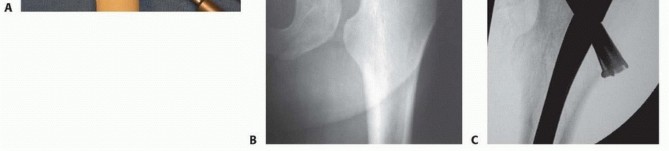

Closed Reduction and Percutaneous Fixation The patient is positioned on the fracture table and reduction is obtained as noted earlier, C-arm visualization is verified, and the leg and hip is prepared and draped in a sterile fashion. Preoperative antibiotics are given. ### Guidewire and Screw Placement Guidewires for cannulated screws are placed in line with the femoral neck axis through poke holes. The wires are placed parallel using a parallel drill guide. The standard screw arrangement is an inverted triangle of three screws. They should be positioned peripherally in the femoral neck with good cortical buttress, particularly against the inferior and posterior neck. Starting points below the lesser trochanter should be avoided owing to risk of subtrochanteric fracture postoperatively ( TECH FIG 1A-C).

TECH FIG 1 • A. Sawbones lateral view of the proximal femur showing configuration for three parallel guidewires before placement of cannulated screws. The wire starting points form an inverted triangle. B. Intraoperative AP fluoroscopic view showing position and depth of the guidewires. The inferior wire runs right along the inferior cortex of the femoral neck—the “calcar” (

arrow

). C. Intraoperative lateral fluoroscopic view showing guidewire position. The posterior wire is directly adjacent to and supported by the posterior cortex of the neck. Care is necessary to ensure that the guidewire does not go outside of the neck and then reenter the femoral head.

Once the position of the wires is verified in two planes by fluoroscopy, small (1 cm), full-depth incisions are made at each guide pin, and the soft tissues are spread to the bone. The lateral cortex may be drilled in patients with dense bone. Self-drilling, self-tapping cannulated screws are placed by power over the guidewires. Washers should be used in the more proximal, metaphyseal locations ( TECH FIG 1D,E). Screws should be long enough so that all screw threads are on the proximal (head) side of the fracture.

### TECH FIG 1 •

(continued)

D,E. Intraoperative fluoroscopic views demonstrating cannulated screw insertion over guidewires. D. AP view showing use of washers in this metaphyseal location. E. Lateral view showing parallel insertion and appropriate depth. A no. 15 blade on a long handle is positioned at the inferior margin of the base of the femoral neck on the AP fluoroscopic image. A small skin incision is made at this level, and the soft tissues are spread down to the joint capsule. With fluoroscopic verification of position, a small capsulotomy is performed to allow drainage of the hematoma from the capsule. A blunt sucker tip can be inserted through this small incision to evacuate any remaining hematoma.